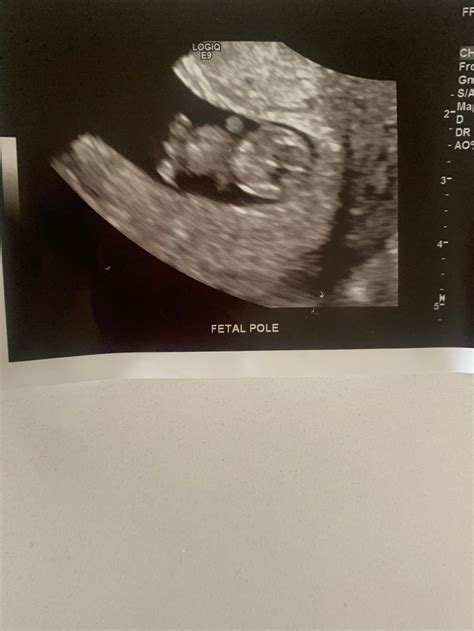

• Fetal Pole: The fetal pole, which is the earliest visible sign of the embryo, should be clearly visible.

During a nine-week ultrasound, several common findings can be observed. These findings provide valuable information about the embryo's development and the pregnancy's progress. Some of these findings include:

• Embryo's Position: The embryo's position within the uterus is assessed to ensure it is properly implanted.

• Placental Development: Early signs of placental development may be visible, although the placenta is not fully formed at this stage.

These findings help healthcare providers monitor the pregnancy's progress and identify any potential issues early on.